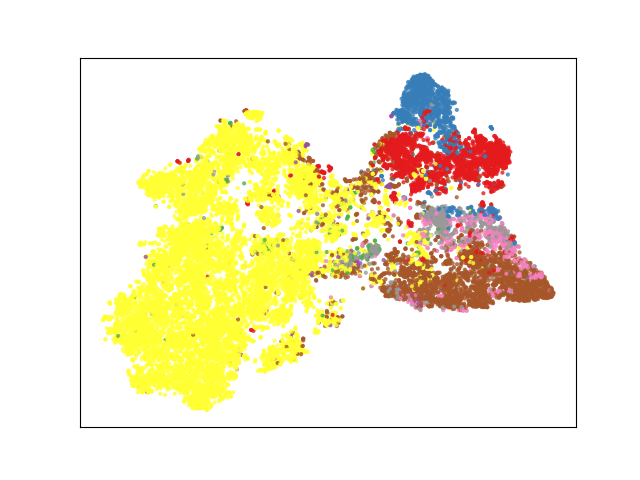

From Table III, we can observe that each major component of our proposed method (i.e., and ) contributes to a more structured representation space in the training process. Specifically, guides unlabeled data to follow the distribution of labeled data, and plays a significant role in generating separated feature representation, as expected.

Recent semi-supervised segmentation approaches in medical imaging have demonstrated promising results by employing various techniques, such as consistency regularization [10, 11], pseudo-labeling [12], and adversarial learning [13]. However, previous methods train the network with the outputs obtained from the final layer, which complicates learning of global features by the network. The proposed method is effective for learning both local and global contexts by embedding voxel-level features with voxel-level feature layers and voxel-level feature discriminators (Table I and Fig. 5). We achieved a more structured representation space (Fig. 7 b) by defining voxel-level feature (including global and local context) relations in the representation space. On comparison with a previous method [13] which also included global contextual information with the discriminator and SDM, our method achieved superior results (Table II), particularly for multiclass datasets. By learning class-specific voxel-level features using BYOL[15] and a multitask discriminator, we achieved a more structured representation space (Fig. 7 and Table III) and precise segmentation results for the multiclass dataset (Table II and Fig. 6). This indicates that our method is effective for learning feature relations across different classes. Moreover, as presented in Table IV, significant performance improvements can be observed for simultaneous use of the voxel-wise feature discriminator and voxel-wise representation learning; this implies that the unlabeled data distribution follows the labeled data distribution as we intended (Table III), thereby embedding rich feature representation. In future studies, we can improve the results by suggesting a more efficient method to enable unlabeled data to follow the distribution of labeled data.